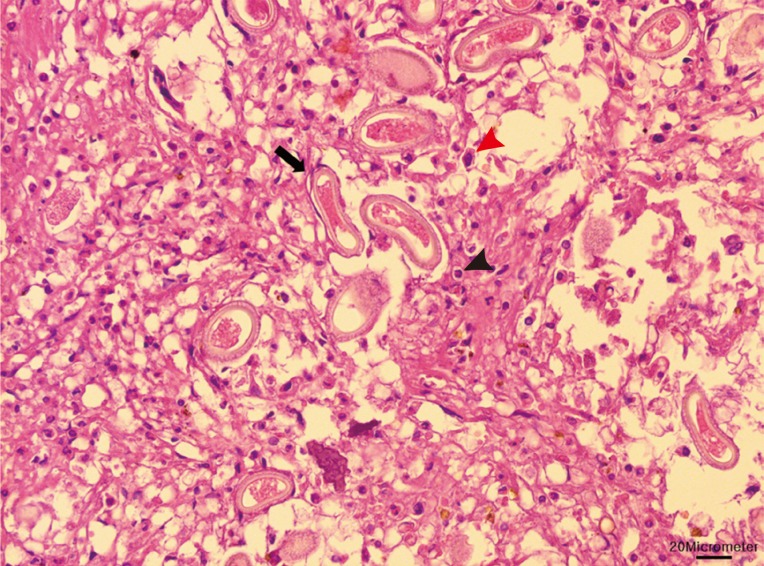

Due to the damages they cause and the potential transfer of diseases they can carry, nutrias are controlled and eradicated by the Ministry of Environment and local governments. Ten dead adult nutrias were sent to our laboratory, which were obtained from a baited wire cage trap in a wetland around the Nakdong River (N35°18'47.80" E128°47'16.83") during 12-13 March 2013. The sample set included 5 males and 5 females (2 of which were pregnant). The livers were collected at necropsy, formalin-fixed, and paraffin-embedded. Sectional specimens of 3 µm thickness were stained with hematoxylin and eosin. Basophilic mineralization was found in the bile ducts in 2 of the nutrias. In the liver of 1 nutria, there were multifocal granulomatous lesions, distributed randomly (

Fig. 1). The infiltrating cells were predominantly lipid-laden macrophages, eosinophils, and several multinucleated giant cells. The lesions consisted of numerous eggs and necrotic hepatocytes. The eggs were lemon-shaped, unembryonated, and polar plugs occurred at the ends of both long sides (

Fig. 2). Longitudinally sectioned parasites were found in a different lesion, which was mainly infiltrated by macrophages (

Fig. 3). The eggs were identified as those of

C. hepatica.

Fig. 1Macrophages (red arrowhead) and eosinophils (black arrowhead) infiltrated in the granulomatous lesion. Numerous eggs (black arrow) and necrotic hepatocytes were seen in the lesion. Bar=20 µm.